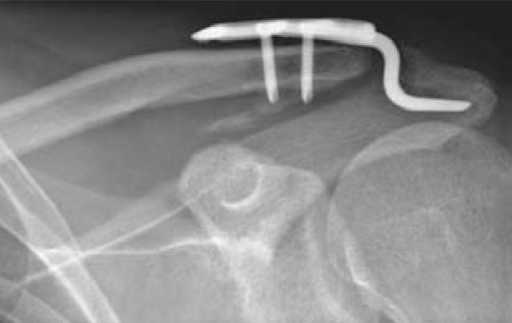

Re: осложнения после фиксации акромиального конца ключицы

Недавно наткнулся на такого рода "новшество" - пластинка от АО для фиксации разрывов акромеально-ключичных сочленений.

Детальнее по ссылке

фото приложил.